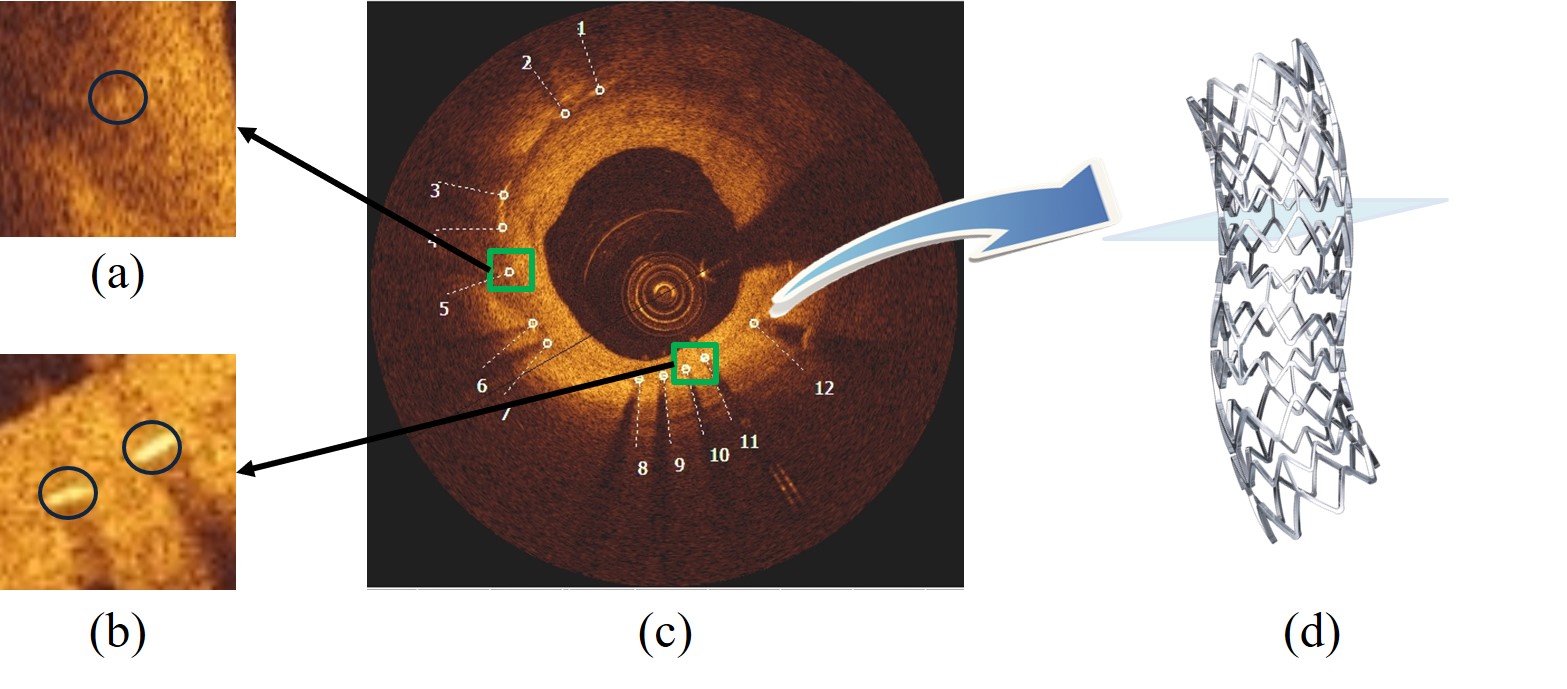

Accurate assessment of neointimal coverage after stent implantation in intravascular optical coherence tomography (IVOCT) images is important to ensure the safety and efficacy of the Percutaneous Coronary Intervention procedure [8]. Unfortunately, manual assessment requires the detection and analysis of thousands of struts within the stent, which is a challenging, tedious and time-consuming task. As shown in Fig. 1, the stent struts are small, and the visual characteristics of the region covering the thick intima (innermost layer of the artery) may make the struts inconspicuous.

Refer to caption

Figure 1: Common vascular features in IVOCT images. The middle image (c) shows the manually labeled stent struts (12 in total), with two green bounding boxes of struts (a) and (b).